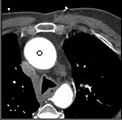

Samples for ascending aorta detection (black circle):

Cluster of candidate points in the ascending aorta.